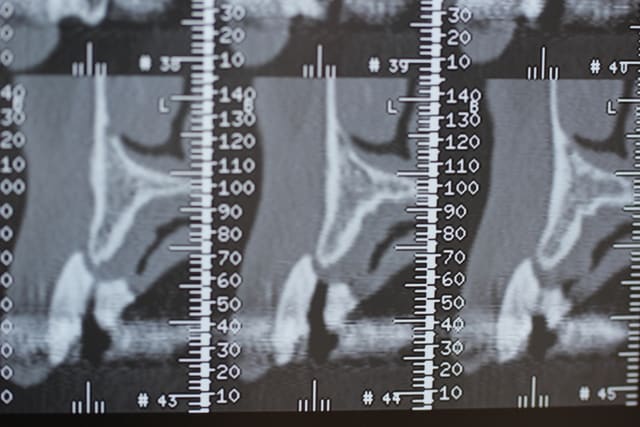

On est en 13 14 15, patiente d'une soixantaine d'années, sans antécédents médicaux ni dentaires. Un peu frileuse pour les grosses chirs mais elle était néanmoins partante pour les implants.

Ce sont les dernières coupes qui correspondent au site de la 13